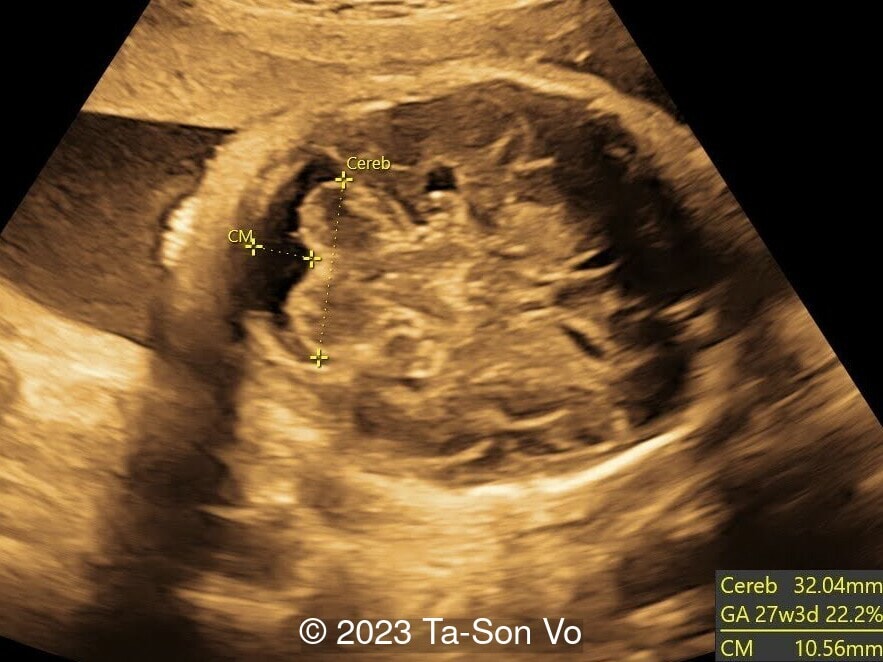

Level 2 ultrasound at 23 weeks and 28 weeks of gestation revealed thick nuchal and prenasal skin (Image 1), frontal bossing (Image 1,2), facial dysmorphism with a short nose, anteverted nostrils, flat nasal bridge, and long philtrum (Image 3,4), hypertelorism (Image 5), mega cisterna magna (Image 6) and polyhydramnios (Image 7). There was neither congenital diaphragmatic hernia nor cardiac defects with only mild tricuspid regurgitation (Image 8). Fetal biometry demonstrates a large head with rhizomelic limb shortening (Image 9).